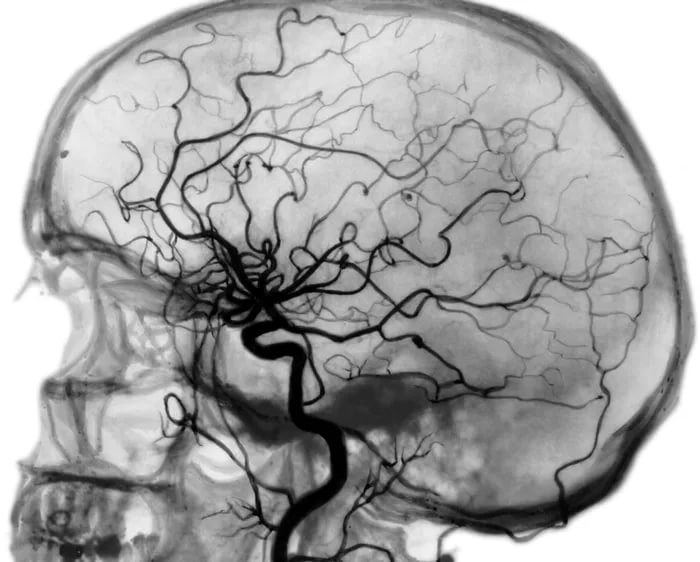

Церебральная ангиография сосудов мозга: полное руководство по диагностике

Столкнулись с необходимостью пройти ангиографию сосудов головного мозга и ищете полную информацию? Наша статья подробно объясняет суть метода, показания, как проходит процедура, и что означают ее результаты.